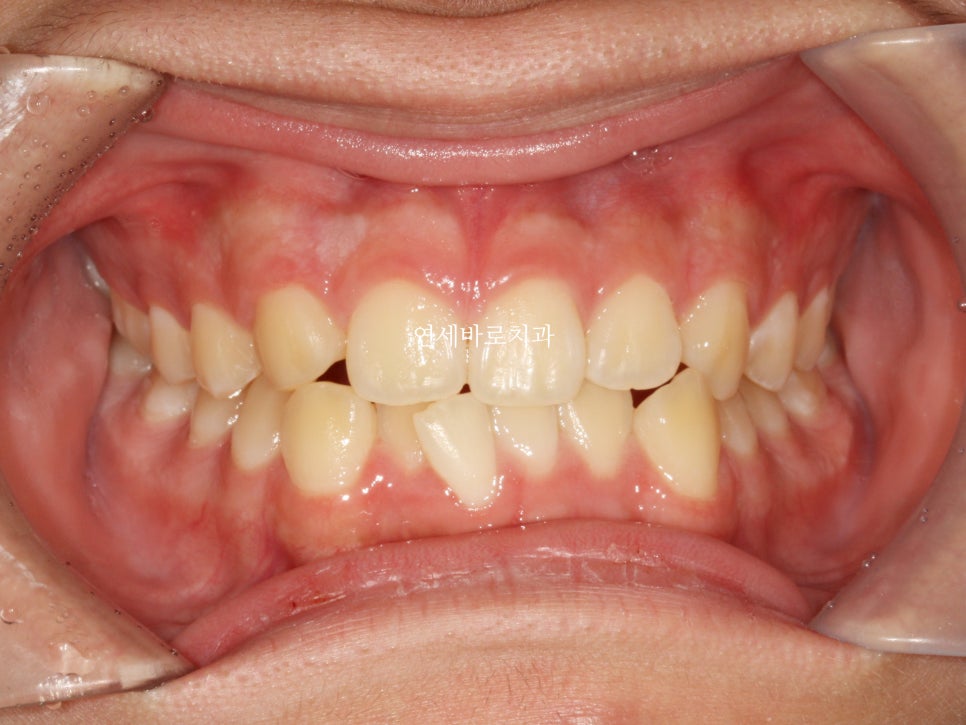

모든 치료가 마무리 된 시점과 처음과의 비교입니다.

비대칭이 많이 개선된 것으로 보이며,

화살표 부분이 원래 치아가 하나 더 있어야 하는 곳인데 없는 부분을 나타내는 곳입니다

그리고 아래쪽 앞니는 아이의 골격과 치아관계를 고려하여 일부러 공간확보를 하지 않았습니다.

발치를 하기로 했거든요